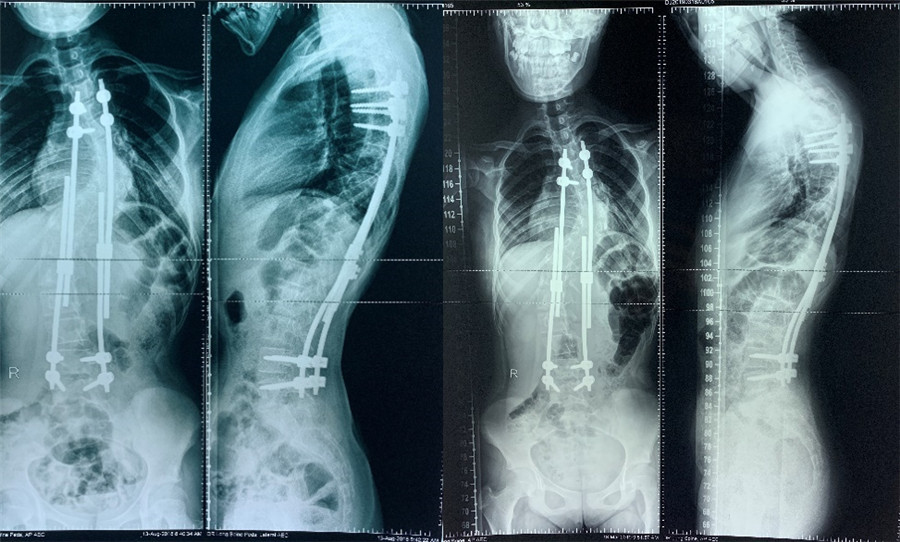

2019年06月第2次生长棒延长术 2020年01月复查